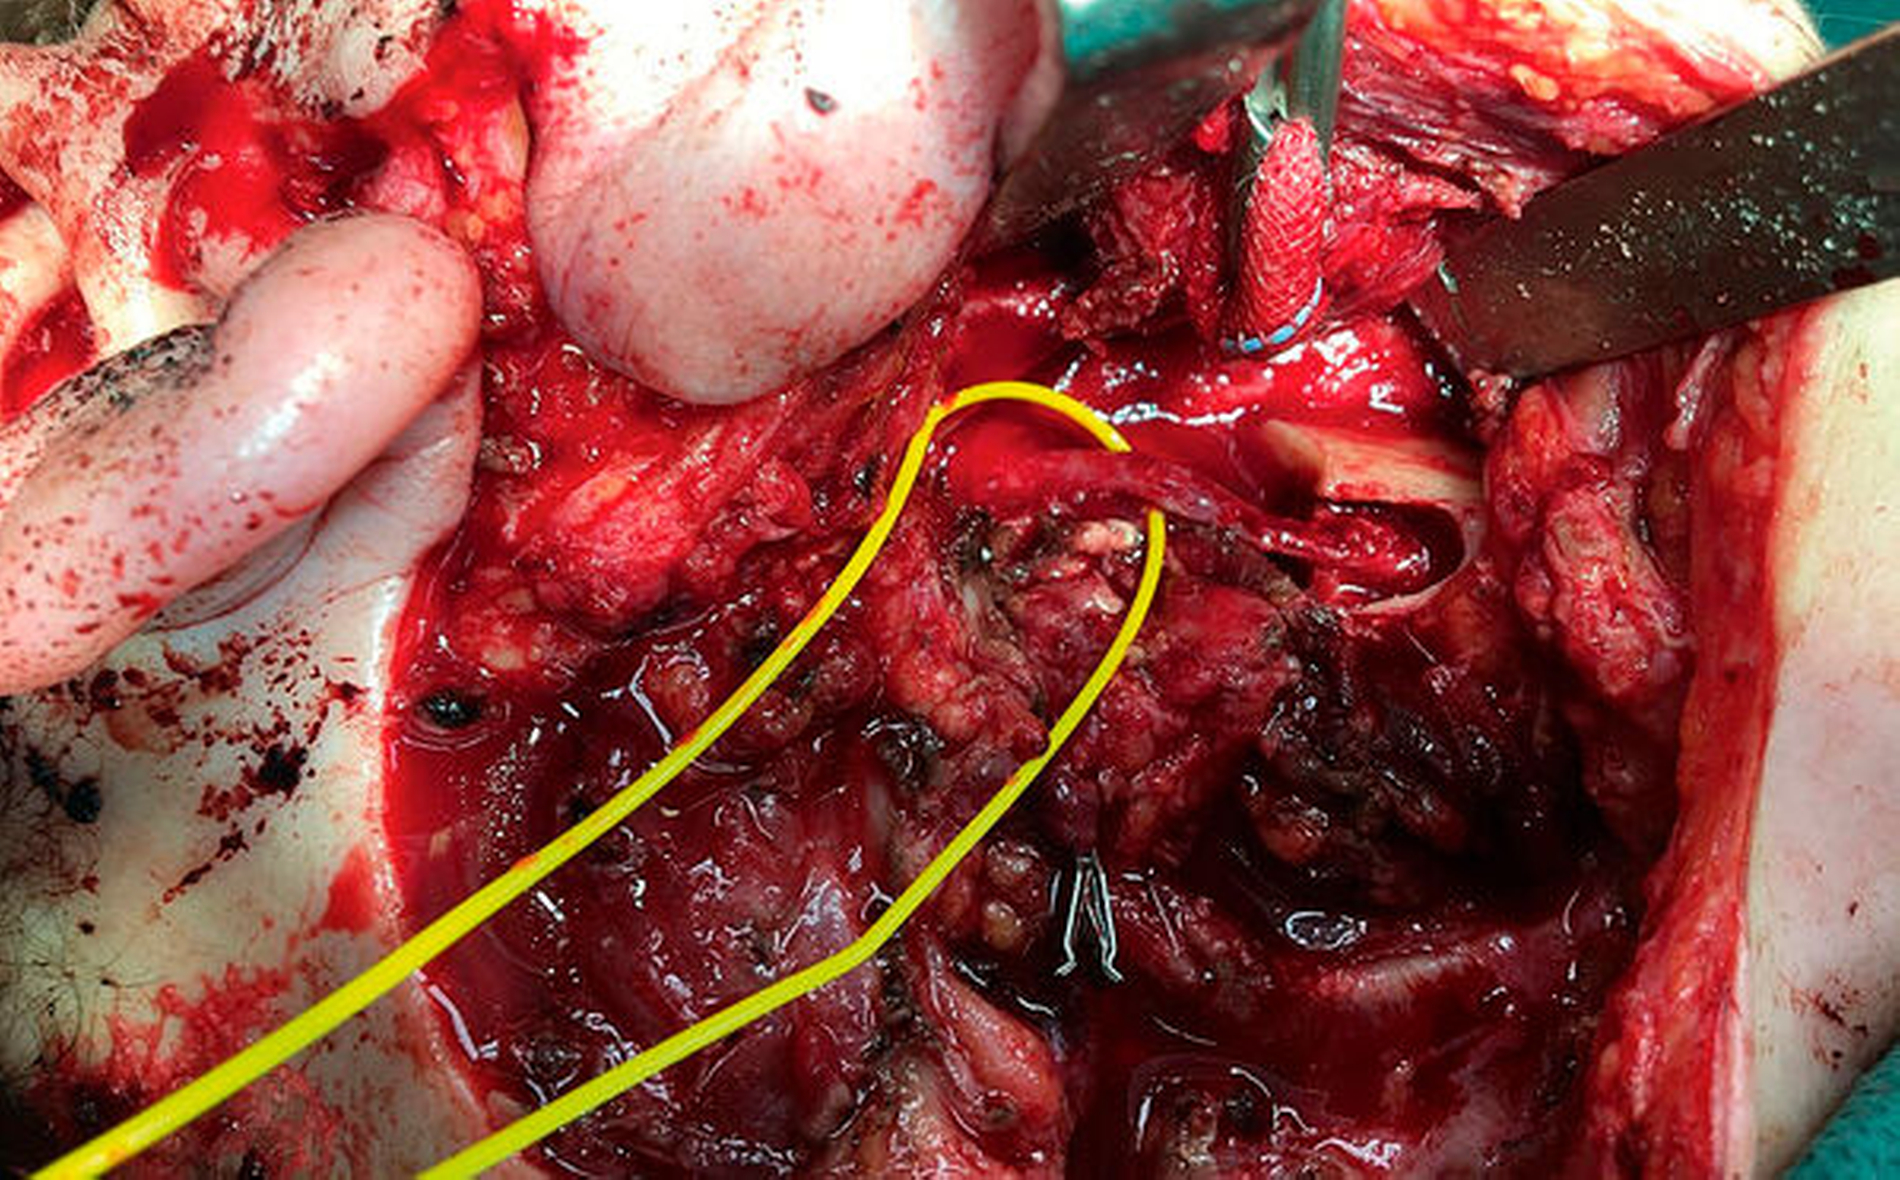

Über einen submandibulären, nach kranial bis präaurikulär extendierten Zugang erfolgte die Exploration des rechten Unterkiefers vom Kieferwinkel bis zum Proc. condylaris. Abbildung 3 zeigt die rechte Kieferwinkelregion mit dem bereits freigelegten Nervus alveolaris inferior. Eindrücklich kommen die zystisch-osteomyelitisch affektierten Lakunen im Bereich der äußeren Kortikalis zur Darstellung. Nach erfolgter Lateralisation des Nervus alveolaris inferior wurde die Kontinuitätsresektion des Unterkiefers von regio 048 bis unmittelbar unterhalb des Proc. condylaris vorgenommen (Abbildung 4). Die histopathologische Aufarbeitung des Resektats bestätigte die Diagnose einer chronischen Osteomyelitis. Der entstandene knöcherne Defekt wurde unmittelbar mit einem an die Facialisgefäße mikrochirurgisch-reanastomosierten Fibula-Transplantat rekonstruiert (Abbildung 5).